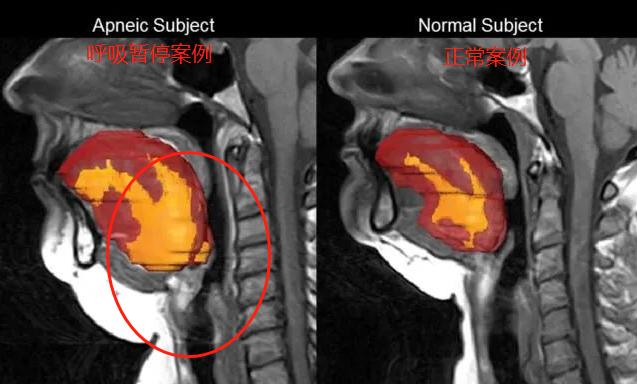

在我们进入“深度睡眠”时,全身的肌肉会放松下来,包括舌根肌肉。

如果舌根肌肉放松得太过分了,躺着时就会因为重力下垂,妨碍到呼吸道。

呼吸道里流通的空气,撞到舌根肌肉上,振动发声,就成了打呼声。

还有些人自身有点毛病,导致呼吸道比正常人狭窄:

晚上睡觉一躺下,舌根肌肉一放松,就更容易妨碍呼吸道,甚至直接堵死!

晚上睡觉一躺下,舌根肌肉一放松,就更容易妨碍呼吸道,甚至直接堵死! 这种情况,叫“病理性打呼”。